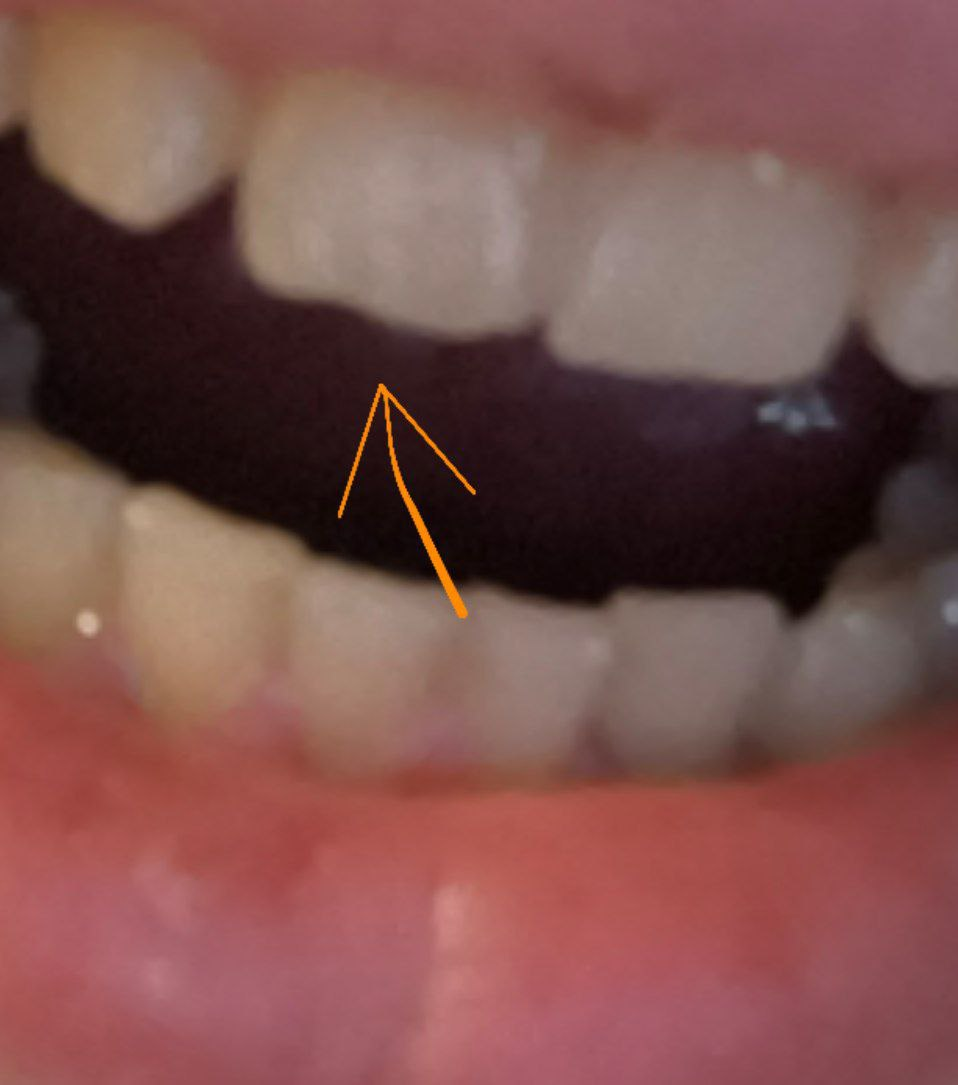

Аноним 08/08/25 Птн 06:11:54 1635233 32

1759678455236.jpg 1558Кб, 2536x3256

2536x3256

1759678455268.jpg 1853Кб, 2252x3434

2252x3434

1759678455308.jpg 217Кб, 1056x1126

1056x1126

1000076562.jpg 534Кб, 1920x1440

1920x1440

1759678455314.jpg 479Кб, 1920x1440

1759678455331.jpg 508Кб, 1920x1440

1759678455339.jpg 562Кб, 1920x1440

Насколько все плохо? Сколько готовить?

Живу в Москве, боюсь. Так что придется искать тех, кто с наркозом работает.